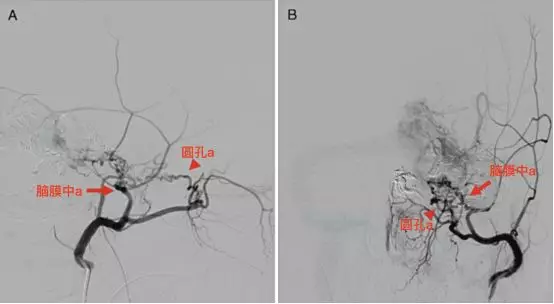

A-B,左侧颈外动脉的侧位和正位。迂曲的脑膜中动脉(直箭)和圆孔动脉(箭头),均供应畸形血管团(Levitt 2011)。

三叉神经分支的动脉血供(Levitt 2011)。V2(星号)由圆孔动脉供血(直箭),V3由脑膜副动脉(空箭)供血。注意圆孔动脉内超选的微导管,以及该动脉特征性迂曲走行。还可见翼管动脉,经翼管走向破裂孔。